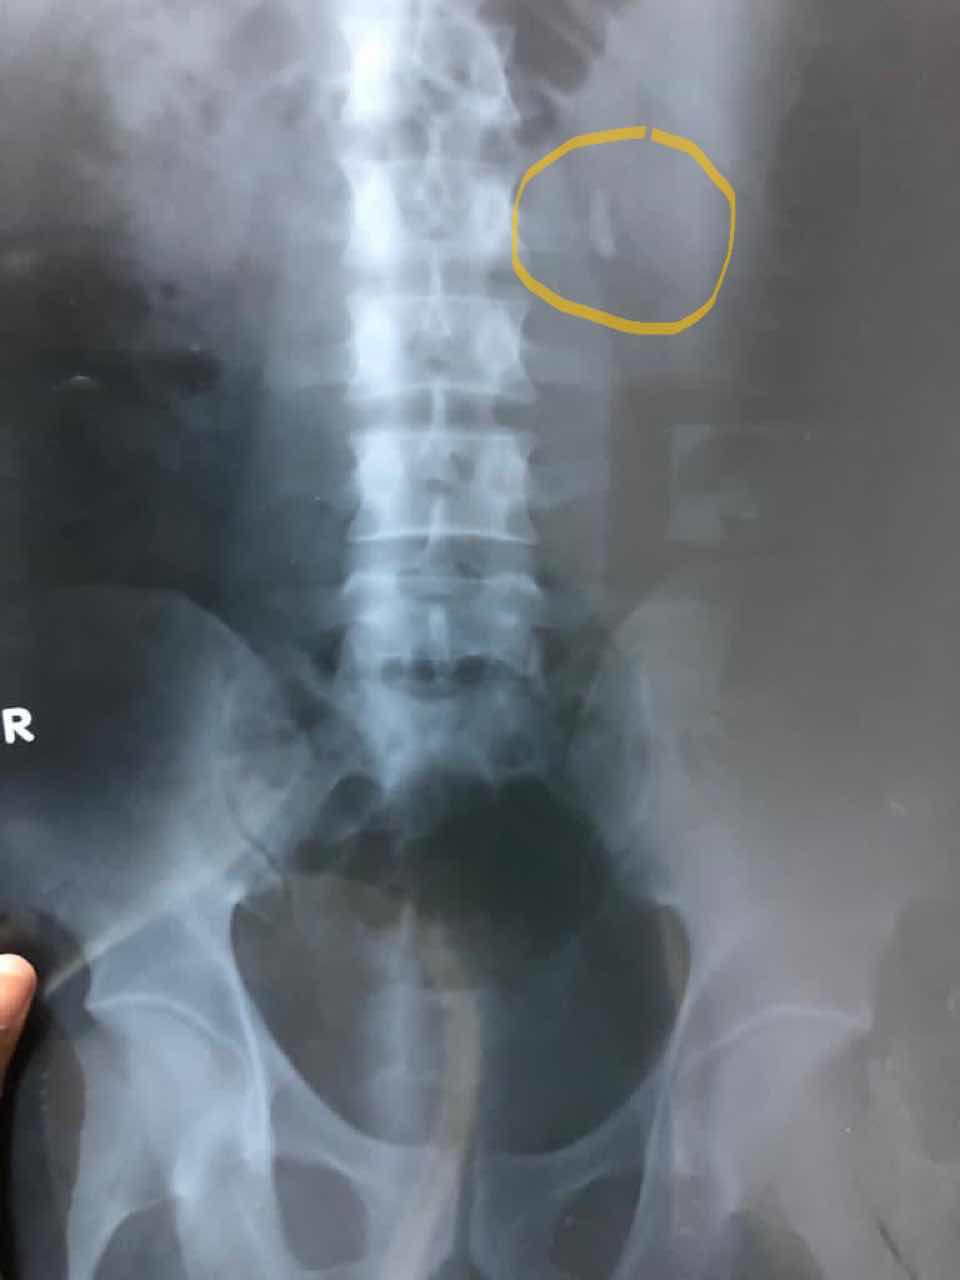

أشعة عادية على المسالك البولية تستخدم لتشخيص حصوات الكلى والحالب والمثانة وتستخدم للمتابعة مابعد العمليات الجراحية فى حالة وجود دعامة بالحالب او بعد التفتيت بالموجات الفوق تصادمية أو فى حالة وجود بقايا من الحصوات تحتاج للمتابعة وتدخل تكاملى آخر

فى هذا المثال توجد حصوة أعلى الحالب الأيسر كما هو مشار إليها